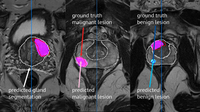

KI-Software vom Hamburger Start-up FUSE-AI hat Premiere auf der RSNA in Chicago Lokalisierung der Prostata und Identifikation von Tumoren dank…